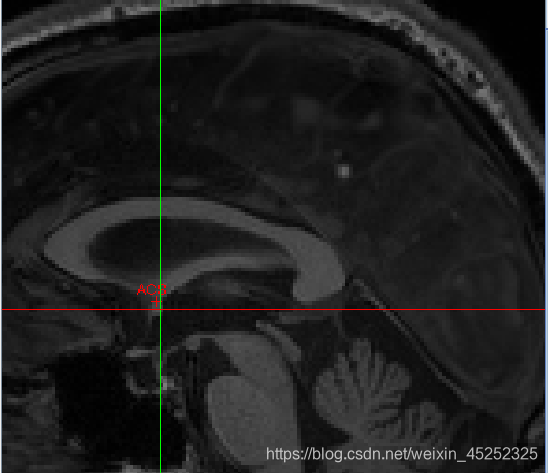

对于这5个点的介绍(图中显示的是矢状面):

一般的nii图中各组织并不是这么明显

AC:

•矢状位:在穹窿下方胼胝体底部寻找AC

•冠状:寻找“胡须”

•轴向:寻找半球间的连接

① 使AC在十字准线的焦点处居中(轴向和冠状)

② 向上移动,直到AC在轴向视图中消失,然后向下移动1像素

③ 设置AC上边缘(superior edge)

④ 将焦点移回AC中间

⑤ 向后移动直到AC在冠状面上消失;然后往前1像素

⑥ 设置AC后缘(posterior margin)

尽量把图放大来选点

找到AC superior edge,点击set

找到AC posterior edge,点击set